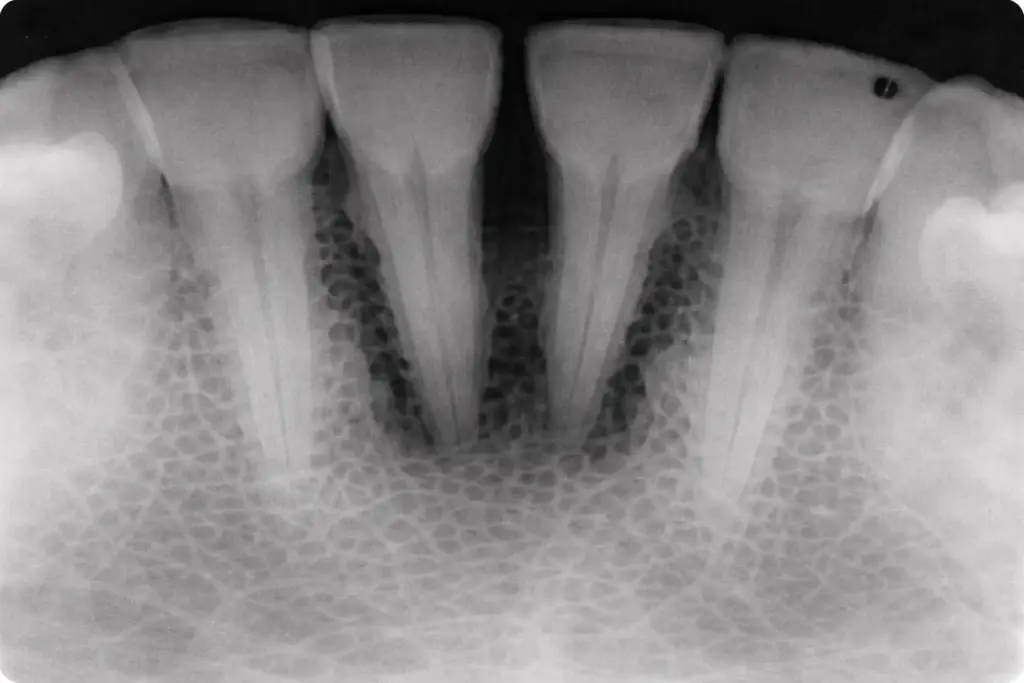

Bone loss around teeth

Detailed gum examination and imaging